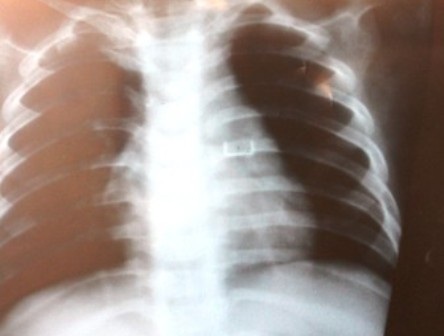

Tuy nhiên, sau khi tiến hành chụp X-quang, các bác sĩ phát hiện trong phổi trái bé Thế Anh có dị vật. Lập tức các bác sỹ đã tiến hành nội soi, sau gần 3 giờ đồng hồ, kíp mổ đã gắp thành công 3 chiếc ghim bằng sắt dính vào nhau từ phổi bé Thế Anh ra ngoài.